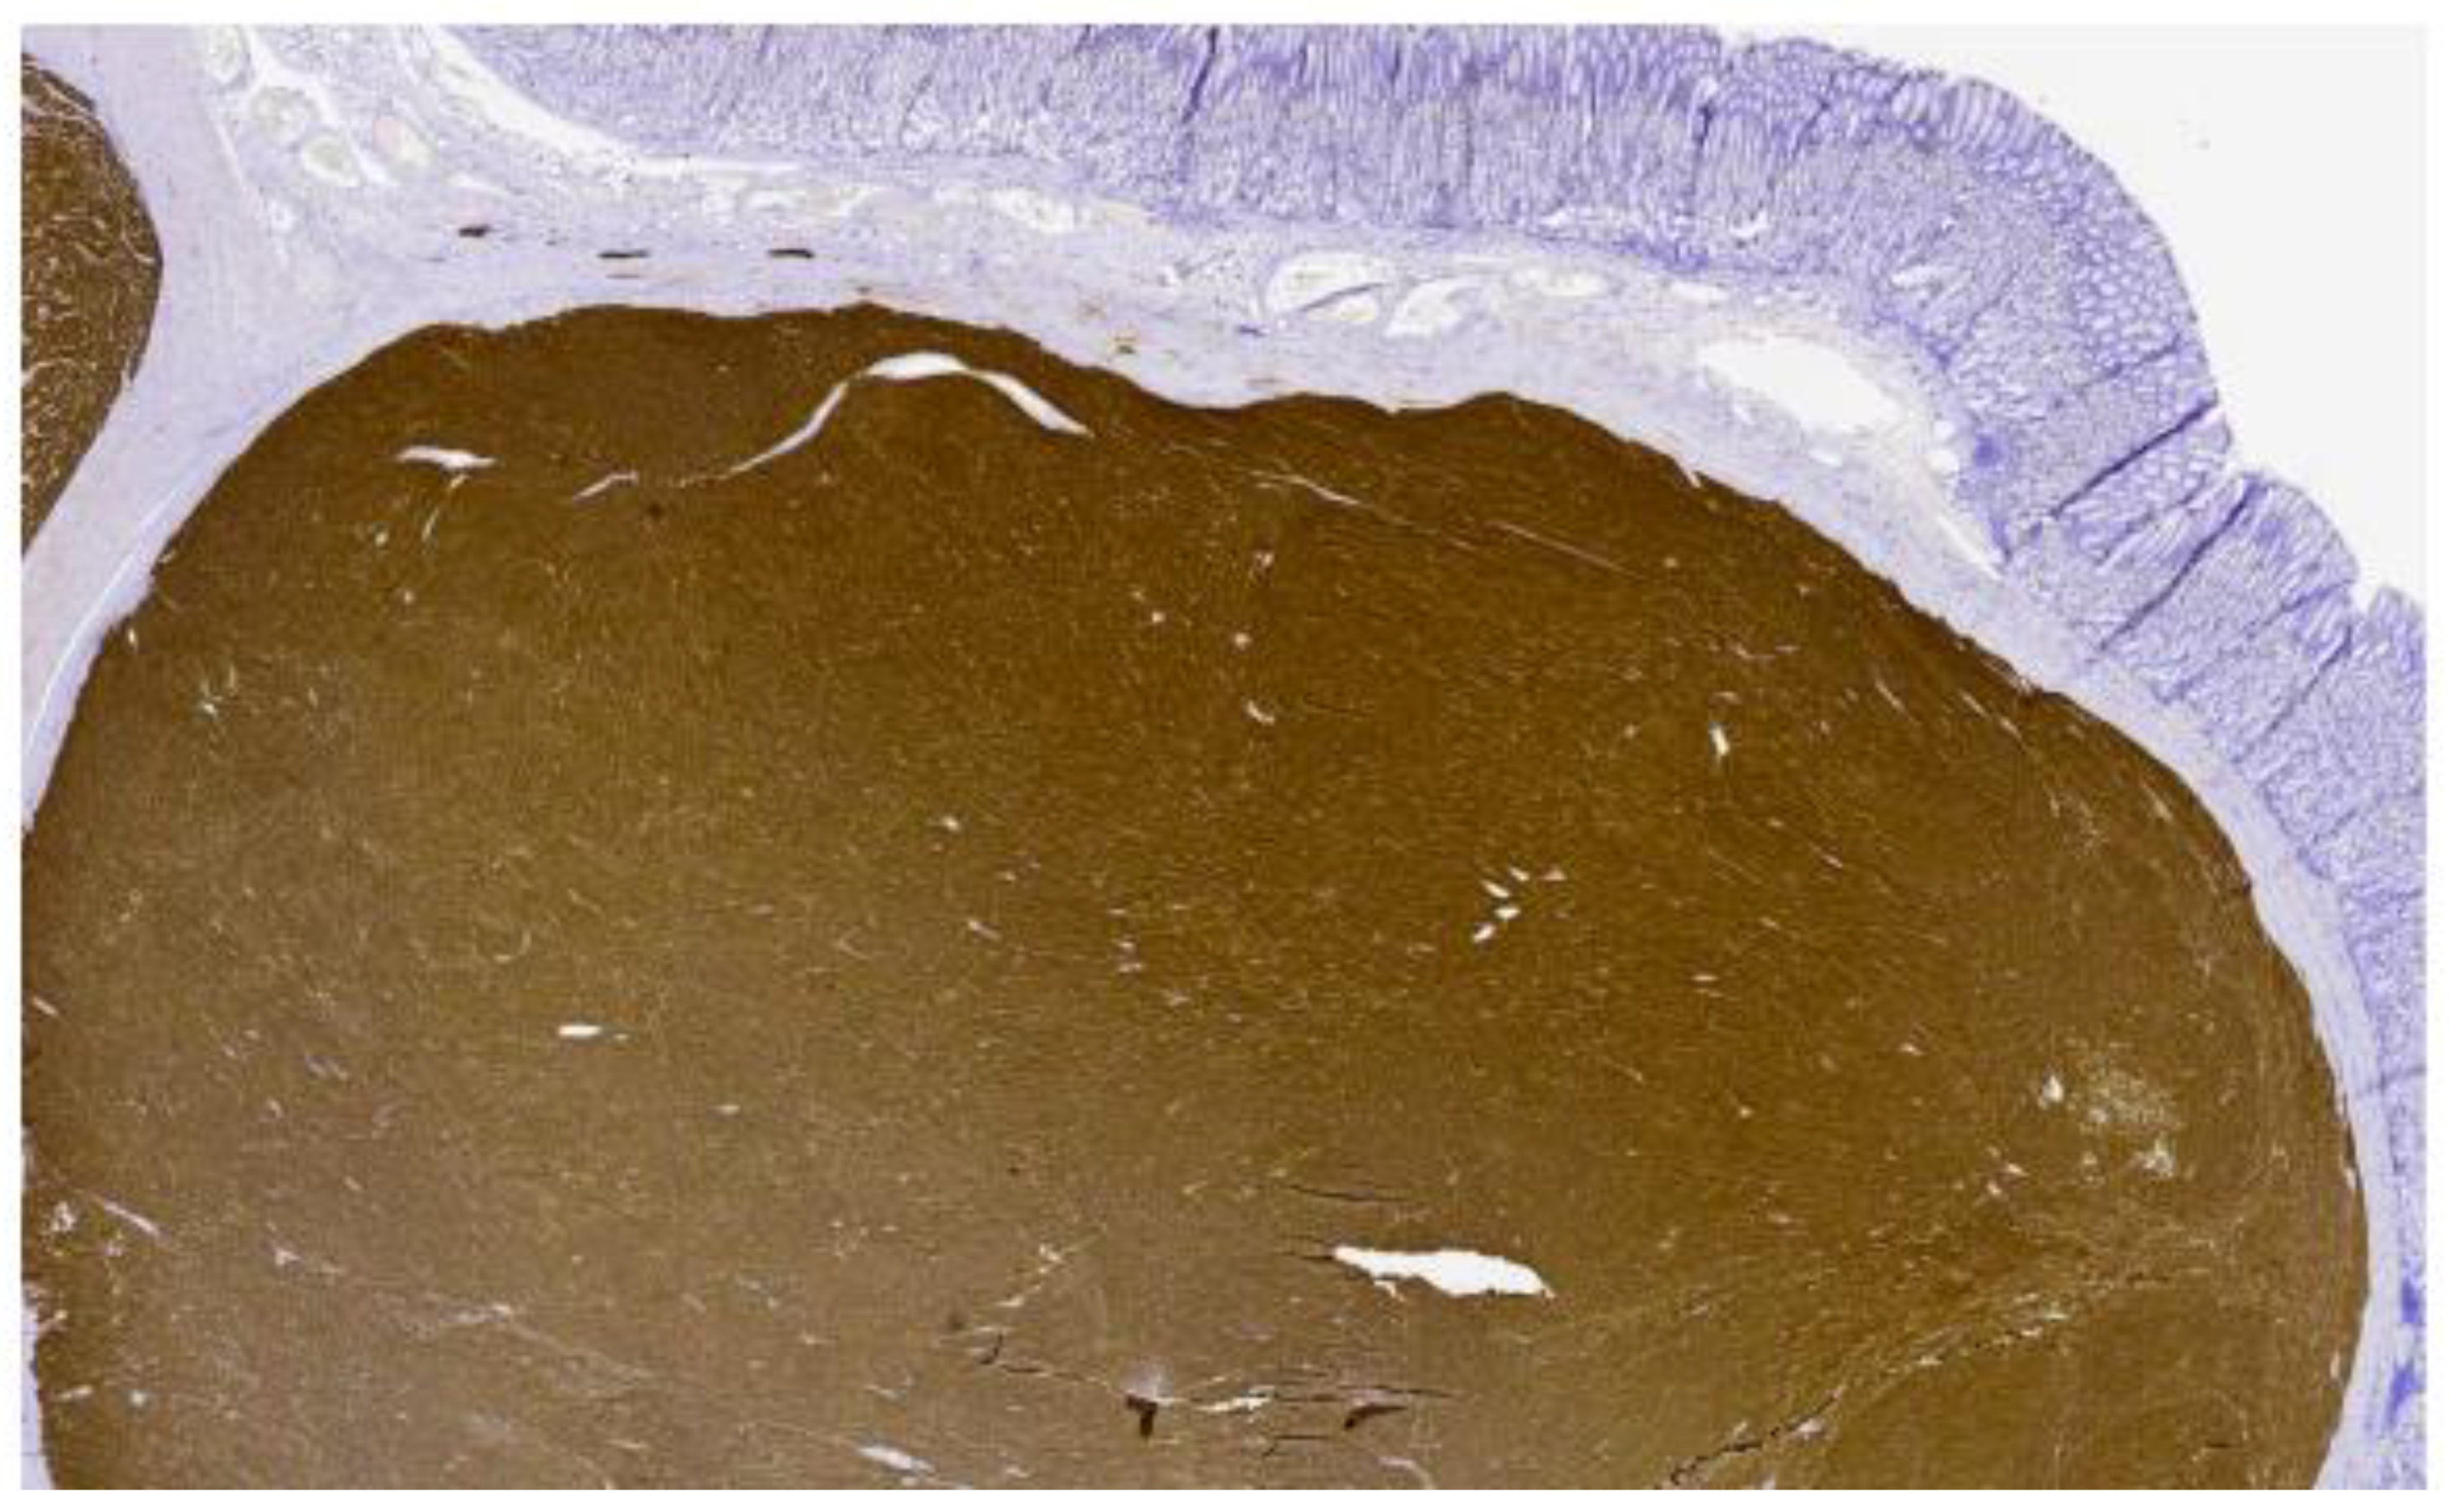

2. Case Presentation